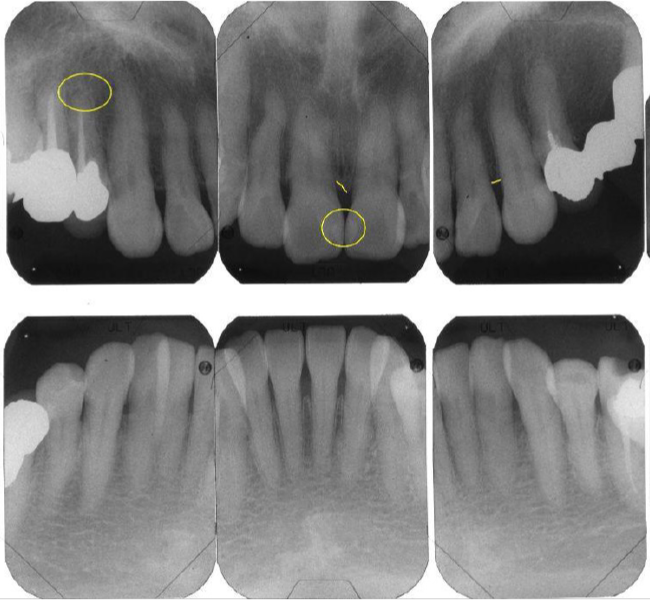

治療前